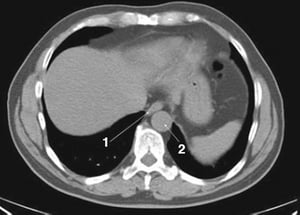

CT-Scan von Abdomen und Becken mit normaler Anatomie ohne Kontrastmittel (Folie 10)

Dieses Bild zeigt die Crura des Zwerchfells (Pfeile).

© Springer Science+Business Media